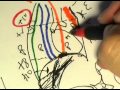

ANATOMY 2.0: MEDIASTINE

By

cuneatos

184K views

15 years ago